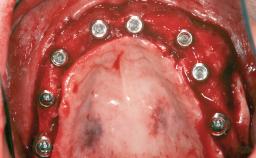

# of Implants 4

Type of Implants One-Piece|Reduced-Diameter

Bone Augmentation Horizontal|Simultaneous|Sinus Floor Elevation|Staged